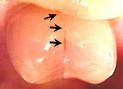

Broken / Fractured tooth.

A tooth that has broken is usually too weak to hold

a filling. A crown will hold the tooth together and prevent it from breaking again. If the fracture involves the nerve, Root

Canal Therapy may be required before the tooth is

crowned. In some cases, a broken tooth cannot be saved

and must be extracted.

| This patient chose not to have the cracked tooth above crowned, and it later fractured. This tooth had to be extracted because it cracked all the way to the root. |